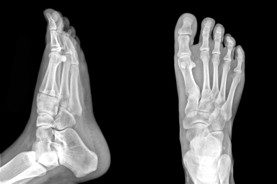

Alberta Foot Doctor & Foot Physical Therapist

The Foot Institute is an association of Alberta Doctors specializing in the medical treatment of the foot and ankle, and is one of the largest groups of foot specialists in Alberta.

The Alberta Foot Institute is dedicated to the medical and surgical treatment of the foot. Our mandate is to provide the best possible medical, surgical and preventative treatment available for our patients. We do this by providing well-trained Doctors who are committed to treat and prevent all types of foot pain, biomechanical disorders, as well as all other problems relating to the feet.

At the Alberta Foot Institute, our Doctors are trained to specifically treat problems associated with your feet or ankles. Below are several of the most common problems that we see on a day to day basis: